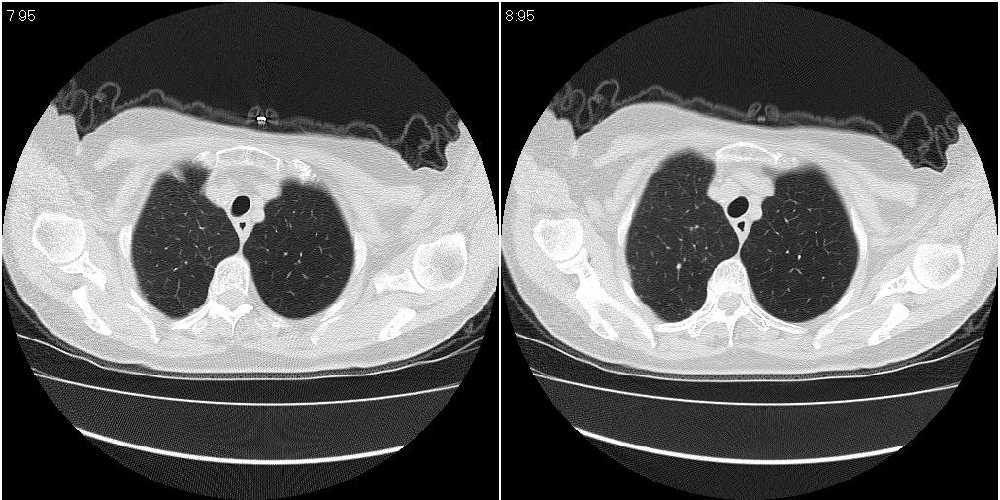

女性,72岁。去年9月份发现肺部病变,诊为肺结核并进行正规治疗至今,但复查后发现ct表现几乎没有变化。

右侧中叶支气管明显狭窄,建议行纤支镜检查!

右中间段支气管局限性狭窄,右中叶支气管亦稍显狭窄,但并未见明显占位表现,半年多了,无变化也许是好事,可能为炎性狭窄,建议继续随访。

双肺继发型tb并右中叶内膜tb,轻度支扩,左下胸膜肥厚粘连。

右中叶炎性改变,支气管狭窄但较光滑,占位可能性不大。

右中间段支气管局限性狭窄,右中叶支气管亦稍显狭窄.

双肺继发性肺结核并右肺中叶节段性肺不张,左下胸膜肥厚粘连。

右肺中叶节段性肺不张,考虑结核或慢性炎症,建议做纤支镜检查。

双肺继发性肺结核并右肺中叶节段性肺不张